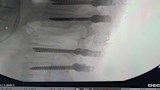

وعقب إجراء الفحوصات والأشعة اللازمة، جرى التدخل الجراحي العاجل بقيادة الدكتور أحمد كمال أخصائي جراحة المخ والأعصاب، حيث تقرر تثبيت الفقرات بشرائح ومسامير مع توسيع القناة الشوكية وتسليك مخارج الأعصاب، بمشاركة الدكتور عبد العزيز المصري أخصائي التخدير وفريق من التمريض وفنيي التخدير والأشعة.